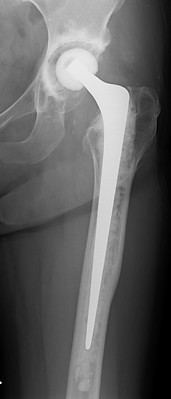

40代女性

両側末期形成不全性股関節症 両股関節をエクセターステム、骨セメントを使用し、再建した。術後14年経過したが、摩耗、弛み、骨粗鬆を認めず元気に働いている。

手術直後